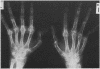

The concurrence of rheumatoid arthritis (RA) and systemic lupus erythematosus (SLE) has been reported infrequently. Eleven patients are described here with both RA and SLE, in whom the diagnoses were separated by one to 24 years. Because of the difficulty in diagnosing RA occurring subsequent to SLE, only patients with classical RA as their initial diagnosis were included. Further difficulties arise because arthritis is common to both diseases and may be deforming in SLE, antinuclear antibodies (ANA) are not uncommon in RA, and rheumatoid factor (RF) may be seen in SLE. Nonetheless, judicious application of the American Rheumatism Association (ARA) criteria allows both diagnoses to be made in the individual patient. In our patients there was erosive arthritis in nine, rheumatoid nodules in five, and urinary abnormalities in 10. Serological evidence of RA and SLE with positive RF and ANA and raised DNA antibodies was universal, all patients had haematological evidence of SLE, and all but one decreased serum complement levels. These cases suggest that the concurrence of RA and SLE is not as rare as previously considered and may occur more often than expected by chance alone.

Images in this article